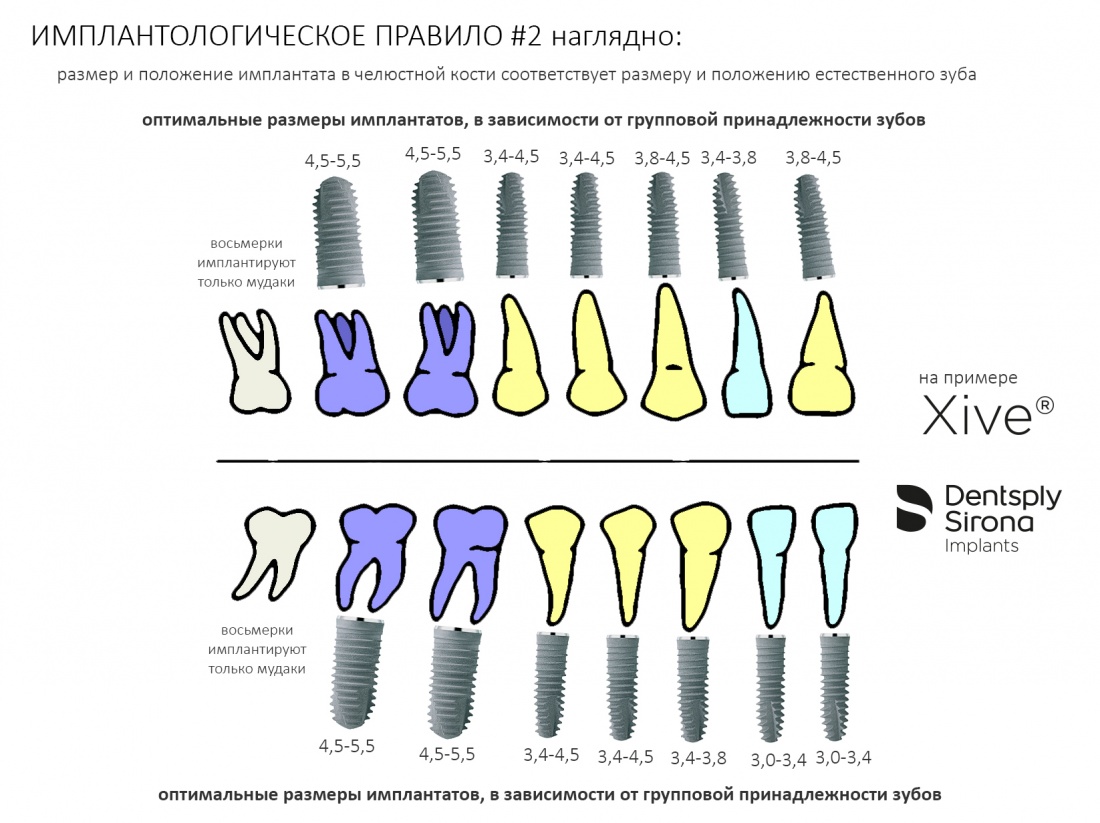

Если серьезно, то при подборе имплантатов, их размер имеет такое же значение, как и положение. Не отрицая важность всех остальных параметров (см. статью про Микро- и Макродизайн имплантатов), далее мы будем оперировать двумя параметрами — длиной L и диаметром импланта D. Казалось бы, всё просто и понятно, ибо существует имплантологическое правило #2:

размер и положение имплантата в челюстной кости должны соответствовать размеру и положению естественного зуба.

Как-то так:

причём, мопед не мой, похожая схема есть на сайте dentpslyimplants.com (применительно к системе Astratech EV):

и даже в рекомендациях к имплантационной системе Dentium:

Но, с другой стороны, кто читает эти рекомендации?)))

Проще говоря, бери для больших зубов большие имплантаты, а для маленьких — маленькие. И всё будет в порядке. Я, кстати, неоднократно упоминал это в своих статьях (например, здесь>> и здесь>>).

Во-первых, некоторые имплантационные системы имеют единый по размеру ортопедический интерфейс, вне зависимости от диаметра самого имплантата. Такими имплантационными системами являются, к примеру, Dentium, Ankylos, Bicon etc.

И, если размер ортопедической платформы одинаков, то есть ли смысл так заморачиваться на диаметре имплантата, ведь площадь опоры абатмента мы всё равно не поменяем? И вообще, имплантаты с одним размером ортопедической платформы, вроде как, своим существованием отрицают необходимость подбора по диаметру. И не совсем понятно, почему их вообще в разных диаметрах выпускают:

Причина того, что имплантаты с единой ортопедической платформой могут иметь разные диаметры, очень проста и понятна. Тонкий имплантат под действием нагрузки будет гнуться и деформироваться, в отличие от большего по диаметру. Тонкий имплантат будет менее равномерно передавать получаемую нагрузку на окружающую костную ткань. Это очень легко продемонстрировать на простой столярно-слесарной модели:

Вот почему имплантологическое правило #2 справедливо даже для имплантатов с единой платформой, хотя может показаться, что подбор их по диаметру не столь важен. Инструкция к Dentium это подтверждает.